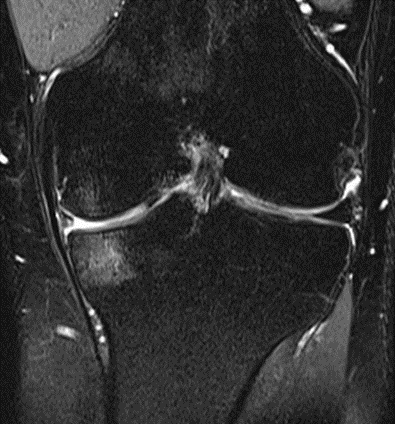

Group 2 exhibited significant reductions as well. Bone marrow edema (BME) was present in 69.23% of patients (9 out of 13 patients) at baseline and significantly lowered to 23.07% of patients (3 out of 13 patients) at the two-month follow-up (p < 0.014). 100% of patients (13 out of 13 patients) displayed signs of synovitis at baseline, statistically significantly decreasing to 23.07% of patients (3 out of 13 patients) at the two-month follow-up (p < 0.002). Effusion was observed in 92.31% of patients (12 out of 13 patients) at baseline and significantly dropped to 30.77% of patients (4 out of 13 patients) at the two-month follow-up (p < 0.011) (Figures 9-11).

MRI scans illustrating the improvements regarding Group 2 are presented below, showing pre-treatment images with evident cartilage defects, pronounced bone marrow edema, and synovial inflammation, followed by post-treatment scans demonstrating improved joint structure, reduced edema, and decreased inflammation (Figures 12-29).

MRIs of Group 2

Figure 12: Female, 59 years, pre-intervention MRI.

Figure 13: Female of figure 12, 59 years, two-month follow-up MRI: MSC plus ChondroFiller® liquid.